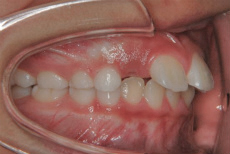

上下あご共にすべての乳歯が永久歯に交換して数か月後の噛み合わせの状態です。

この時点では上あごの12才臼歯である第二大臼歯がまだ生えていません。つまり、歯並びが整ったこの時点で ”もういいですよ” と治療をとっとと終わらせてしまうのはまだ早い ということです。

6才臼歯の後ろに生えてくる予定の12才臼歯がこの時点ではどのように生えてくるかがわからないからです。